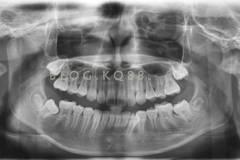

談到早期矯正,涉及到對雙期矯正概念的理解、適應(yīng)癥的把控、各種早期矯正裝置的制作與安裝、患者生長發(fā)育知識的了解等內(nèi)容。

下面這個小患者就存在需早期矯正的問題。通過早期矯正,在不長的時間內(nèi)就達(dá)到極為明顯的療效。她的情況如果等到牙齒替換完畢后再解決,矯治的難度則會非常大。